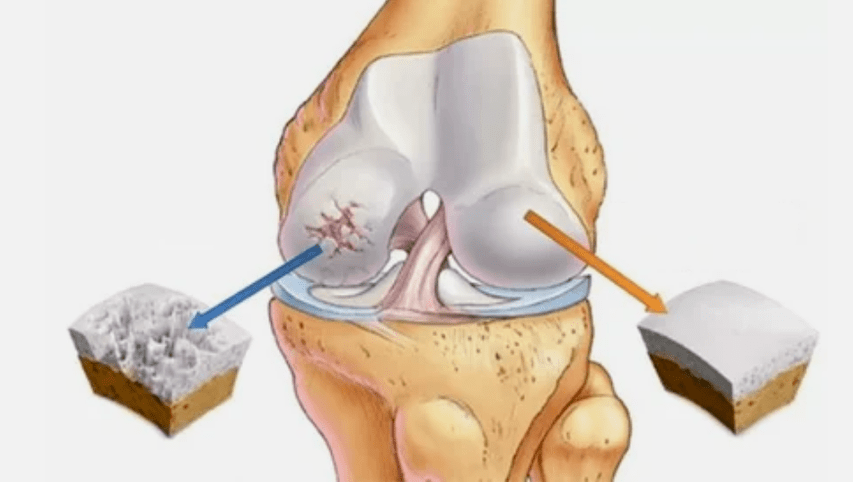

The arthrosis of the joint develops for a long time, initially affecting only hyaline cartilage, then spreads into the bones, includes the synovial sheath, the muscles and the entire capsule of the joints.In the first or early stage of arthrosis, the lesion manifests itself slightly: small pain after hard work, swelling, redness of the skin.Due to ignoring uncomfortable sensations, the joint is deformed, inflamed, carries severe pain, their peak falls in the morning.The disease is characterized by the disappearance of pain after the development of the joint.If left untreated, one completely loses the mobility of the joint.

- The primary lesion affects hyaline cartilage.In the case of blood disorders, there is a deterioration of pathological power.This is the first step or cause that can occur arthrosis.

- Pathologies of hyaline coating.The thinning of cartilage leads to the replacement of its pathological tissues - bone structures.

- Anomalous growths appear on cartilage - osteophytes.

- The emerging violation of the natural anatomy of cartilage and bones provokes the overload of healthy cartilage areas.The destruction of joint tissues without treatment is constantly progressing and leads to damage.

When the degree of disease increases, the pathological processes still deteriorate.In the end, all the cartilage of hyaline is destroyed.